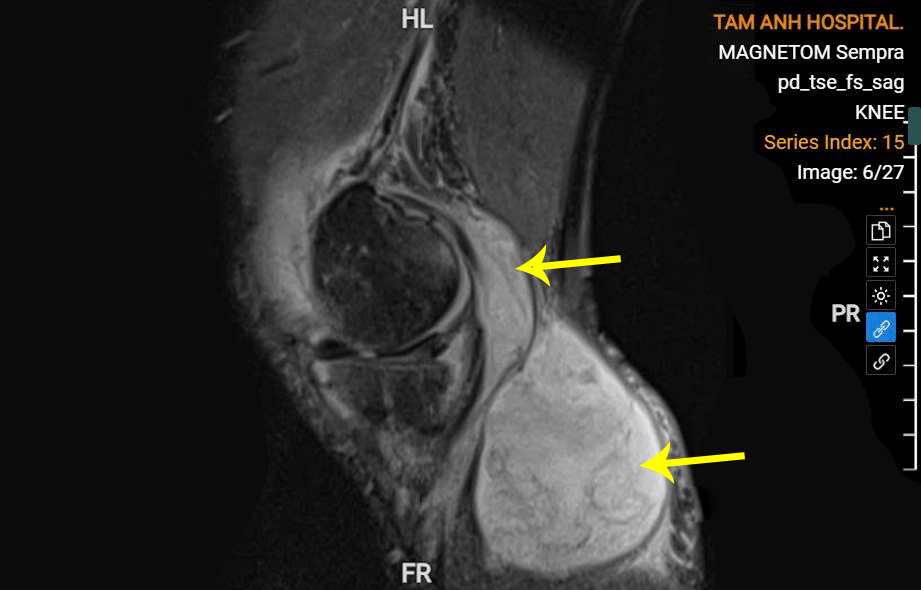

Synovial cyst containing a large pus pocket behind Mr. Trinh's knee. *Photo: Tam Anh General Hospital*

Mr. Trinh, who had suffered from polyarthritis, joint pain, and a synovial cyst in his knee for years, sought treatment. Blood tests at Tam Anh General Hospital Hanoi showed elevated white blood cell count, CRP, and procalcitonin. Further examinations, including ultrasound and MRI, confirmed pus and a large 5x10 cm synovial cyst behind his knee, filled with cloudy pus.